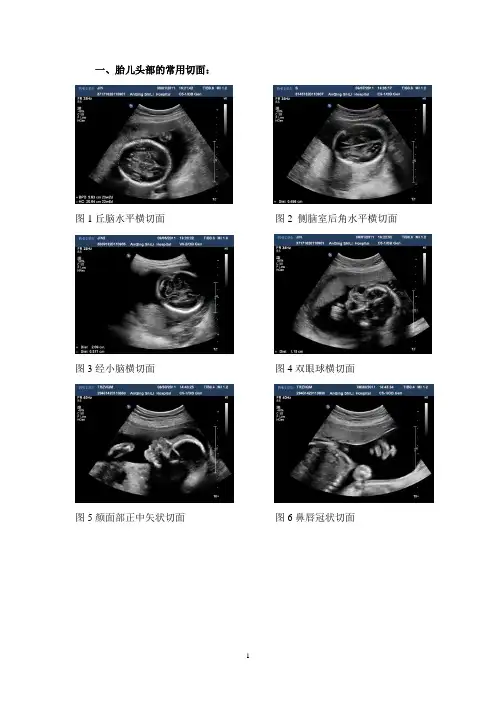

一、胎儿头部的常用切面:

图1丘脑水平横切面图2 侧脑室后角水平横切面图3经小脑横切面图4双眼球横切面

图5颜面部正中矢状切面图6鼻唇冠状切面